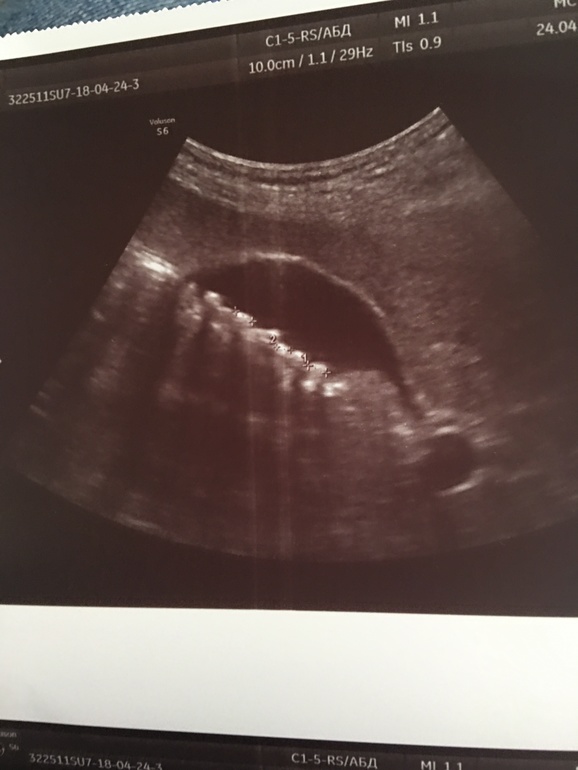

Была на узи. И на тебе!! В желчном камней 10-15. От самых мелких до 1см. Я была в шоке. До беременности все было пусто...

Врач сказала, что полностью камни уже не исчезнут. Там горсть их😏 и есть сантиметровые

P.S.раньше смотрела на ребеночка на узи, а теперь вот на это🤦🏼♀️